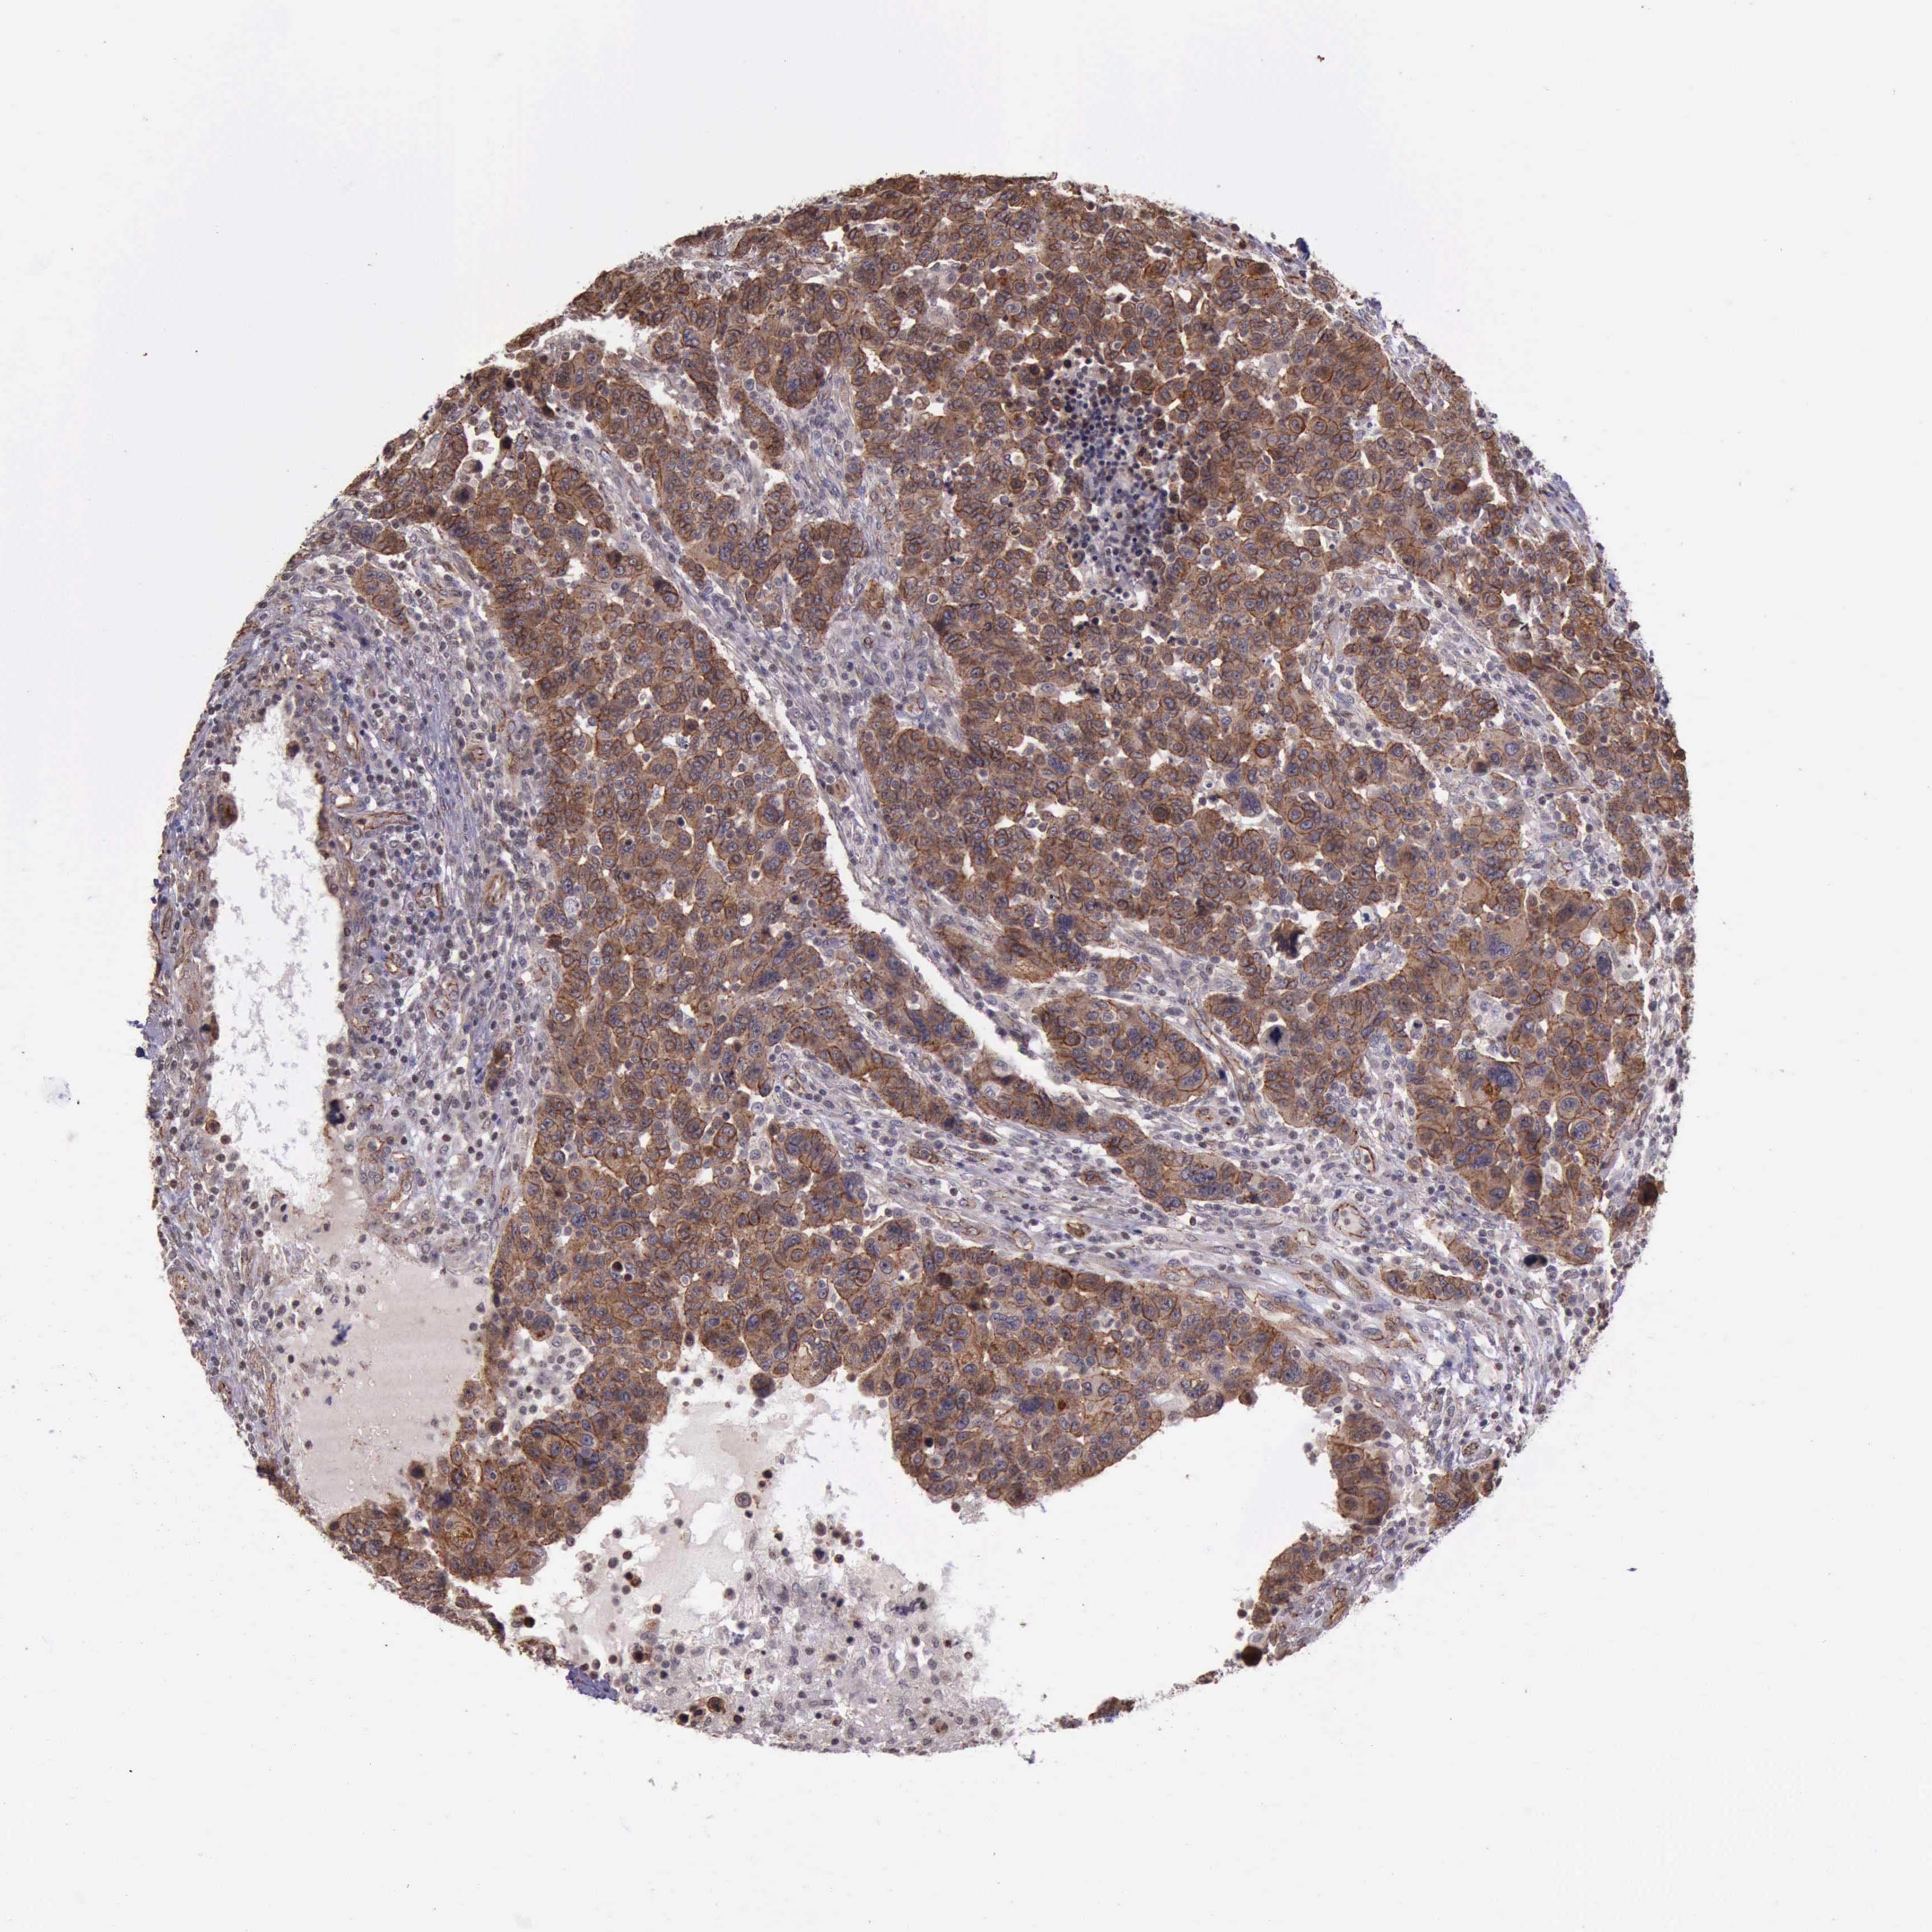

BRCA TCGA BRCA VALIDATION PROTEIN EXPRESSION